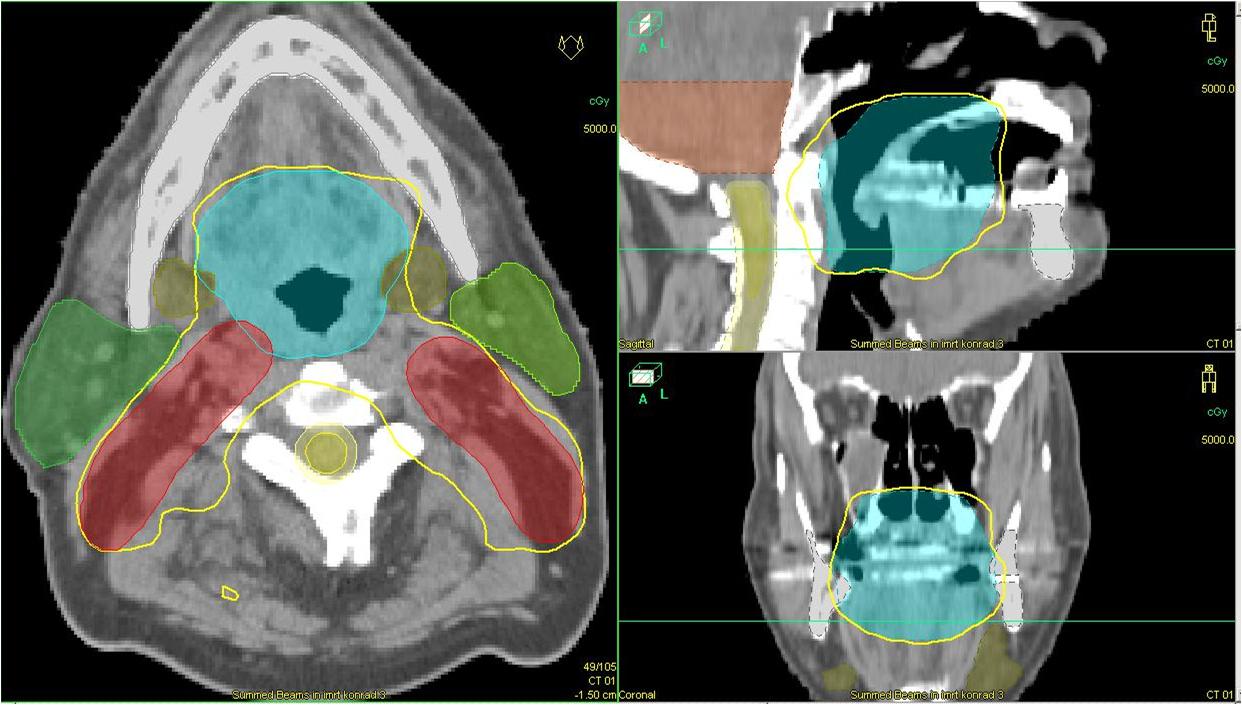

O carcinoma epidermoide de palato mole (CEPM) é uma neoplasia de baixa prevalência que representa a minoria dos tumores que podem acometer a orofaringe. Quando diagnosticados em estádios iniciais, as opções de radioterapia ou cirurgia são aventadas para abordagem terapêutica com taxas de controle locorregional e sobrevida semelhantes. Este estudo tem como objetivo: relatar o caso de um paciente encaminhado ao Departamento de Radioterapia do Centro de Oncologia do Hospital Sírio-Libanês com diagnóstico de CEPM e tratado de forma curativa com radioterapia (teleterapia com técnica de modulação de intensidade de feixe e braquiterapia de altas doses com irídio -192).